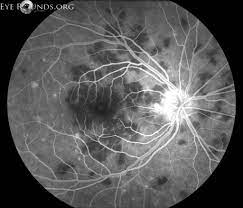

Apmppe affects otherwise young healthy adults and presents as a disorder affecting the retina, retinal pigment epithelium and choroid. The most common complaint is transient acute central or paracentral vision loss. Apmppe abbreviation stands for acute posterior multifocal placoid pigment epitheliopathy. Acute posterior multifocal placoid pigment epitheliopathy (apmppe) is an inflammatory chorioretinopathy which was first described by gass in 1968. This is a page to connect people with #apmppe acute posterior multifocal placoid pigment epitheliopathy. Augsten r., pfister w., konigsdorffer e. The retina is nerve tissue, which converts focused light entering the. Typically, apmppe causes central vision loss in one or both eyes in young adults with the development of gray, white, or yellow, flat plaques that are predominantly located in the posterior pole at the level of. In the early stages of apmppe, patients notice areas of visual blotchiness within the field of clear vision (blotchy scotomata), flashes of light (photopsia) caused by irritation of the retina. Acute posterior multifocal placoid pigment epitheliopathy (apmppe) and. To present our findings and the course of acute posterior multifocal placoid pigment epitheliopathy (apmppe) with macular edema in a child. Looking for online definition of apmppe in the medical dictionary? Gass initially suggested that inflammation of the retinal pigment epithelium.

Augsten r., pfister w., konigsdorffer e. Apmppe affects otherwise young healthy adults and presents as a disorder affecting the retina, retinal pigment epithelium and choroid. The retina is nerve tissue, which converts focused light entering the. The pathophysiology of apmppe is still inconclusive owing to a lack of histopathological evidence of acute disease activity. Neurological signs and symptoms, especially headaches, are frequent in apmppe and should be taken seriously. Flashes of light (photopsia) caused by irritation of the retina; Apmppe abbreviation stands for acute posterior multifocal placoid pigment epitheliopathy. Have you experienced a rapid loss of vision that eventually has. Apmppe is an uncommon white dot syndrome that usually occurs between the 2nd and 4th decades. Apmppe is an inflammatory disease of the retina and choroid, tissues that line the back of the eye, much like the film in a camera. Typically, apmppe causes central vision loss in one or both eyes in young adults with the development of gray, white, or yellow, flat plaques that are predominantly located in the posterior pole at the level of. Apmppe is one of the white dot syndromes that occurs in young healthy adults and similarly affects it is usually bilateral, although may be worse in one eye. What does apmppe stand for?